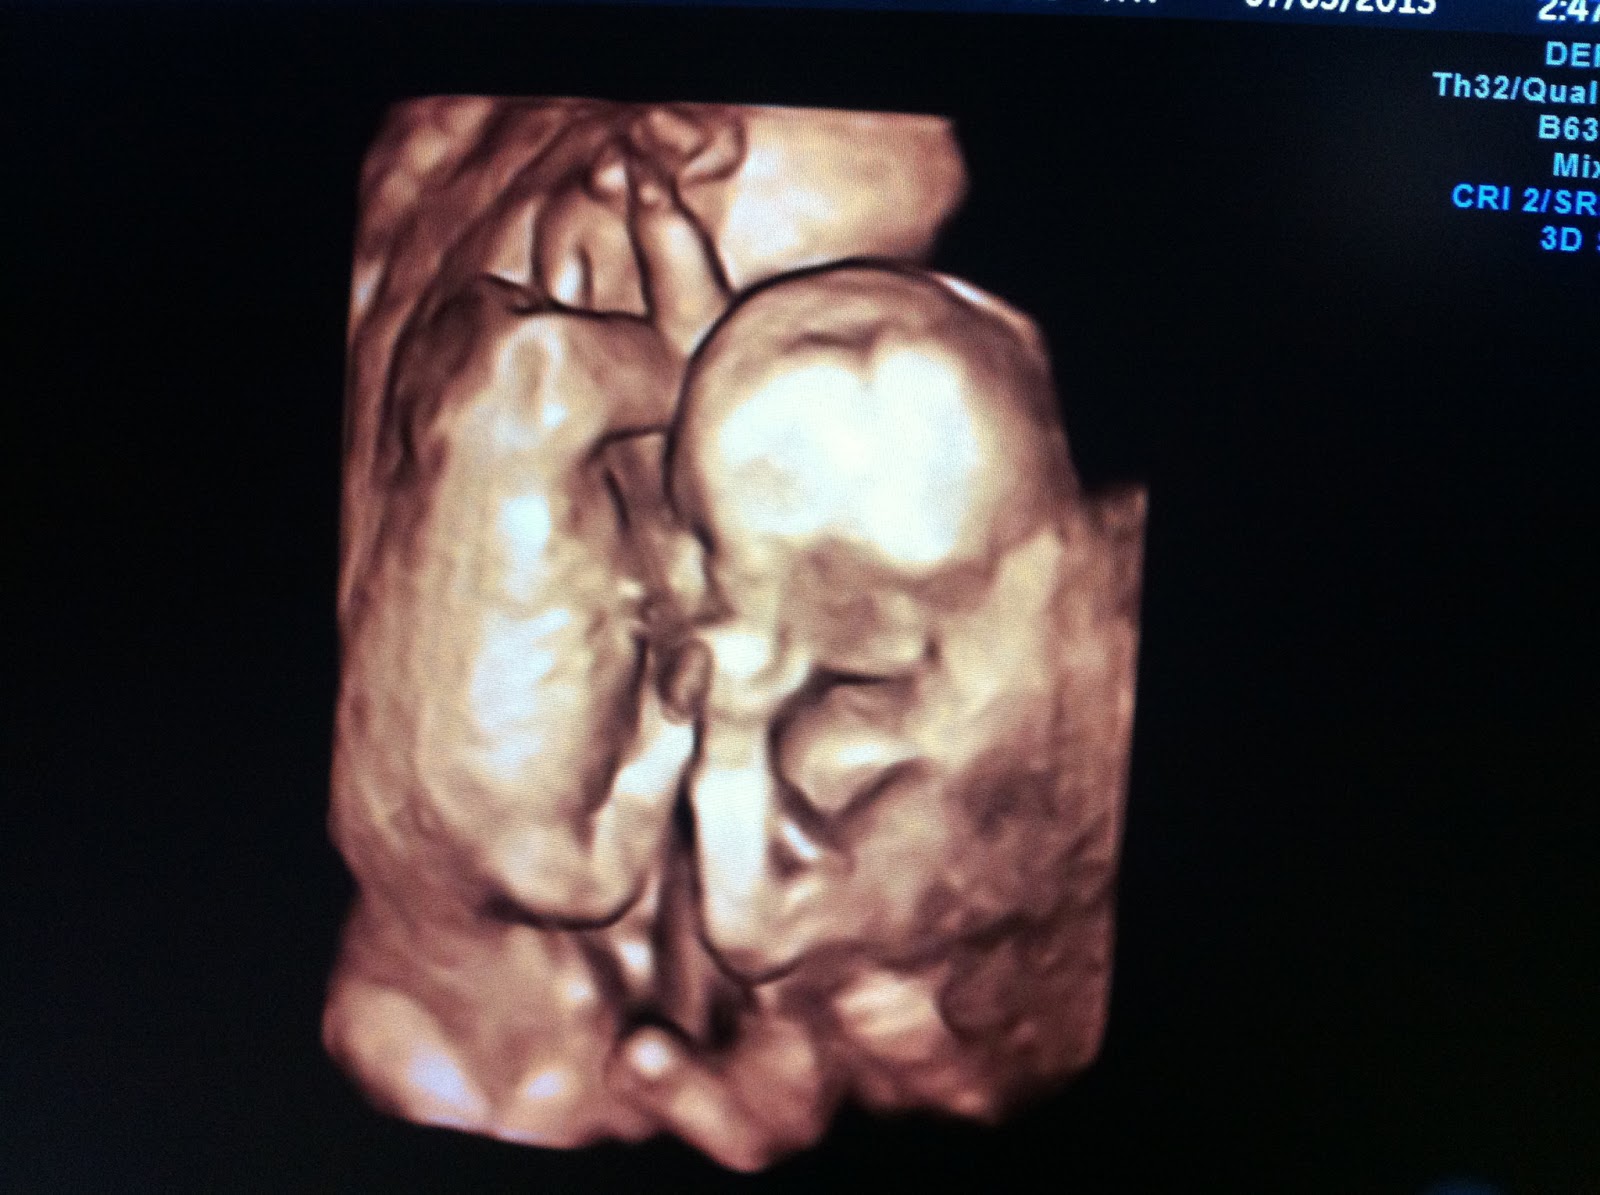

Here's a picture from yesterday's scan. They're lying head to toe in this one and still are all snuggled up.